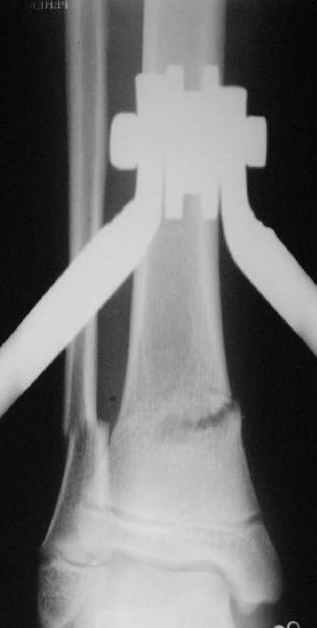

Так как речь зашла непосредственно о травме, см этапные

снимки. Как все было

Фиксация

|

в гипсе